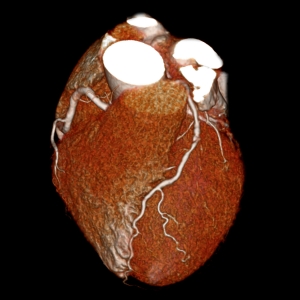

Millions of Americans visit their doctors complaining of mild chest pain. Most are given one of two types of heart exams: a traditional stress test to see how the heart reacts to physical activity, or a state-of-the-art CT scan that provides 3-D images of the heart’s arteries.

Patients who had a CT angiogram — a test that uses X-rays and a special dye to find coronary artery blockages — were no less likely to have a heart attack, be hospitalized or die from any cause within two years than those who had a stress test, according to findings presented in March at the American College of Cardiology’s annual meeting and published in the New England Journal of Medicine(link opens in new window).

Before CT scans came along, the only way doctors could get a peek inside the heart’s arteries was through procedures that involved threading catheters directly into the vessels. Being able to inspect the heart’s arteries in a noninvasive way “was like the holy grail of cardiology,” said study investigator Daniel Mark, M.D., of the Duke Clinical Research Institute.

It is that level of precision that provided the CT test with its one advantage in the trial: more accurately identifying who needed follow-up tests and procedures.